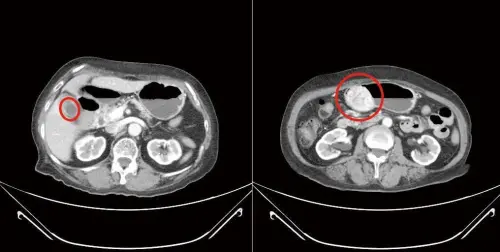

▲林女士不僅胃部長出胃腸道基質瘤,膽囊也嚴重發炎。(圖/國泰醫院提供) 針對胃腸道基質瘤的治療,蔡欣恬指出,以手術切除為主,標靶治療為輔。若經過評估已有遠端轉移,或腫瘤原發位置屬於手術高度危險區域,或腫瘤太大、無法一次手術切除,均可先進行標靶治療,有機會將無法手術的病情轉成可手術,進而產生更好的療效,而據統計,如有標靶藥物介入,整體平均存活率增加3成以上。

72歲林女士3年前經檢查發現有個2公分大的胃黏膜下腫瘤,當時決定持續觀察,但近期腫瘤長大,2個月前因上腹部悶痛且頭暈而就醫,檢查證實腫瘤已近6公分,且膽囊已被結石塞滿,於是接受達文西機械手臂輔助腹腔鏡手術,順利於術後第9天返家,報告則顯示是胃腸道基質瘤合併慢性膽囊炎,未來仍需追蹤。